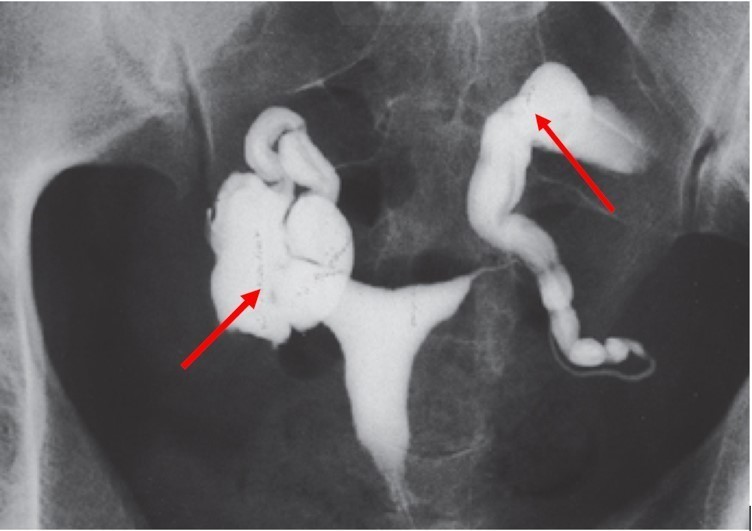

La patiente réalise également cet examen

Question 5. Quelles sont les affirmations vraies ?

On voit deux hydrosalpinx (v. fléchage sur la figure 4)

Il s’agit d’une hystérosalpingoGRAPHIE = radio

L’hydrosalpinx peut entraîner des écoulements dans la cavité utérine et entretenir une inflammation qui est délétère pour l’implantation d’un embryon. L’hydrosalpinx peut également empêcher la rencontre ovule-spermatozoïde dans l’ampoule tubaire

La cavité utérine semble bien opacifiée sans image de défect